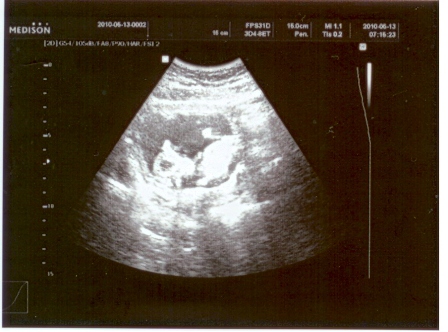

Reggel voltunk uh-n. Ma nem megyek melóba, szóval a képet majd csak holnap tudom scannelni.

Hozzáteszem, olyan sz@r a kórházi uh, hogy gyakorlatilag semmi nem látszik rajta.

Ha a csaj nem mondja, h mi merre van, akkor nem tudtam volna megállapítani! De láttuk a mi kis ufó fejű gyönyörűségünket!!!!

Aludt éppen. Mondta is a nőci, h szép nyugis baba...

Szóval: látszólag és mérésileg minden oké nála! 6,7 cm, Down-kórnak nyoma sincs, arányos a kis teste. Törökülésben voltak a lábai.